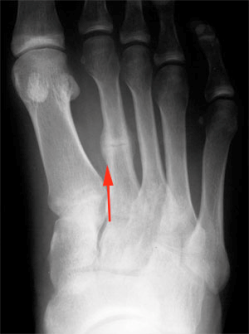

Una persona con una fractura por estrés podría notar lo siguiente. Fractura de estrés 2º metatarsiano Observa el intento de reparación creado alrededor del hueso estresado y fracturado 2º metatarsiano del pie Es la fractura de estrés más conocida y frecuente El metatarsiano es un hueso del pie (El equivalente al metacarpiano de la mano). Descrita por primera vez por el médico de Prusia Breithaupt en 1855, la fractura por estrés es muy común en los reclutas militares y atletas La lesión generalmente afecta a las extremidades inferiores, pero también puede aparecer en las costillas y las extremidades superiores Los lugares más comunes para esta lesión son las tibia, el peroné, metatarsos.

Fractura de estrés 2º metatarsiano Observa el intento de reparación creado alrededor del hueso estresado y fracturado 2º metatarsiano del pie Es la fractura de estrés más conocida y frecuente El metatarsiano es un hueso del pie (El equivalente al metacarpiano de la mano).